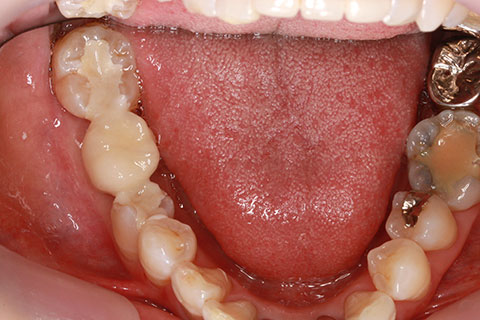

オールセラミックの症例2

- 年齢・性別

- 45歳男性

- 治療期間

- 2ヶ月

- 抜歯

- なし

- 治療費

- 70.4万円

- 備考

- 前歯8本の歯列不正によるセラミック治療

- 治療内容

- 歯質を削除し、セラミック冠をセメント合着

- 施術の副作用(リスク)

- 知覚過敏、歯髄炎、荷重負担